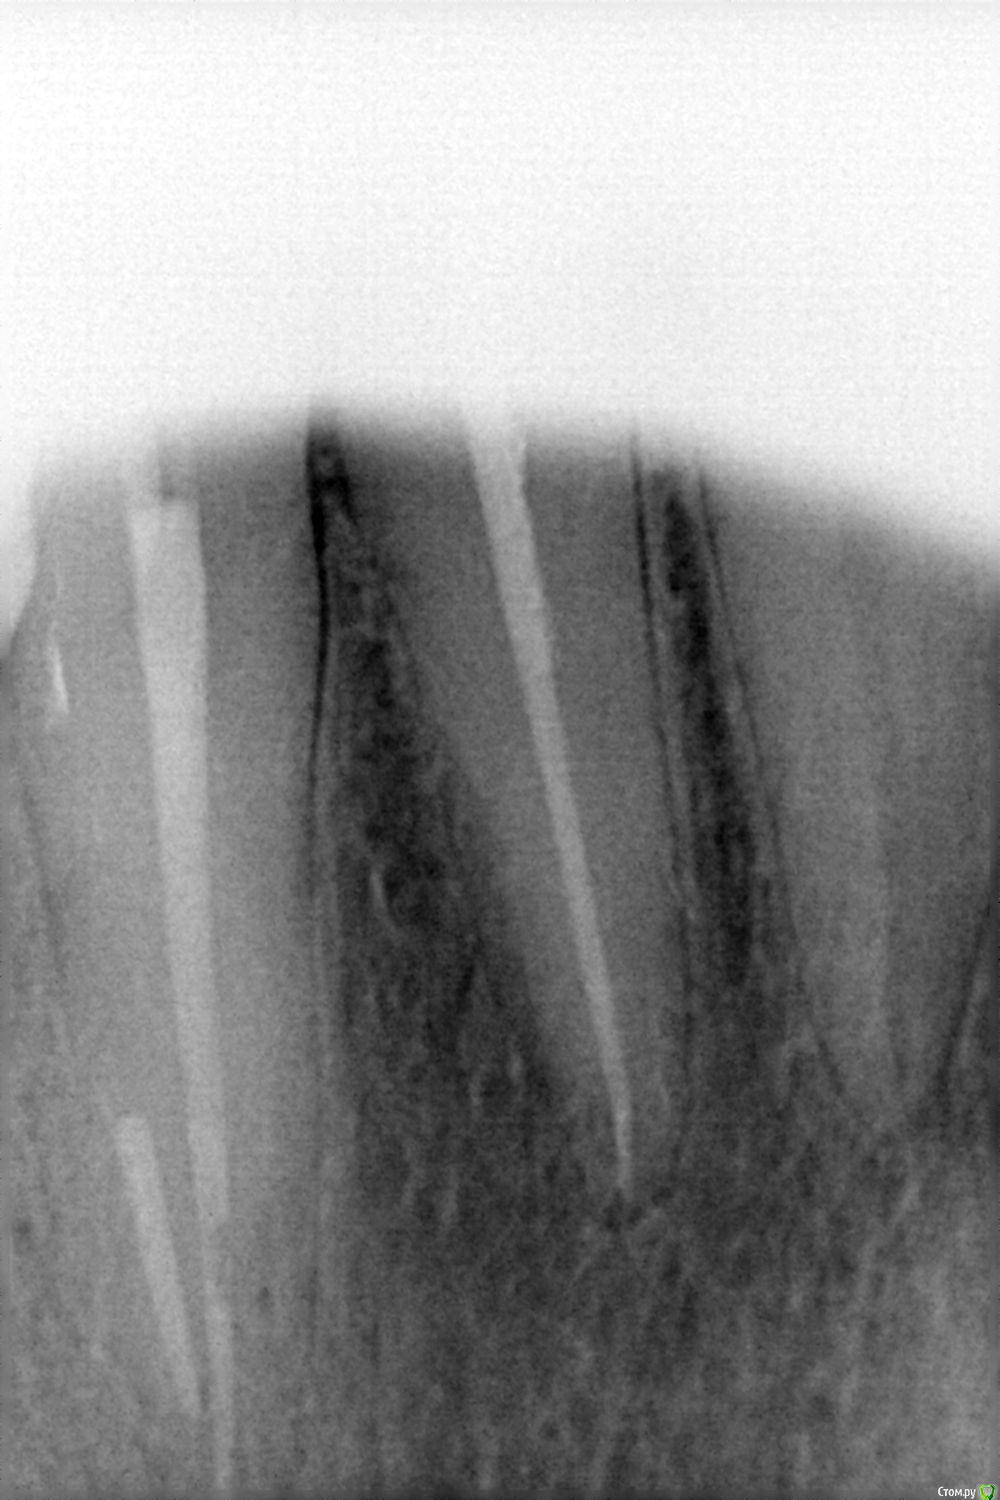

Пять месяцев назад пролечен 23 зуб (был пульпит). Две недели назад промерзли ноги и в этом зубе появилась ноющая боль, без причин, появляется и исчезает сама по себе. Пару дней назад появилась чувствительность при надкусывании и пульсация. Была у двух врачей. Первый предположил пульпит в 22 зубе (там старая глубокая пломба), но предложил подождать, т.к. сильной боли нет и на снимке все хорошо. Второй врач считает, что воспаления нет, давайте понаблюдаем. На снимке 24, 23 и 22 зубы.